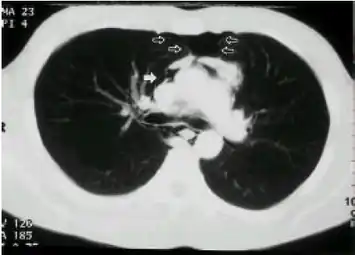

CT scan showed pneumomediastinum blank arrow (and pneumopericardium) -